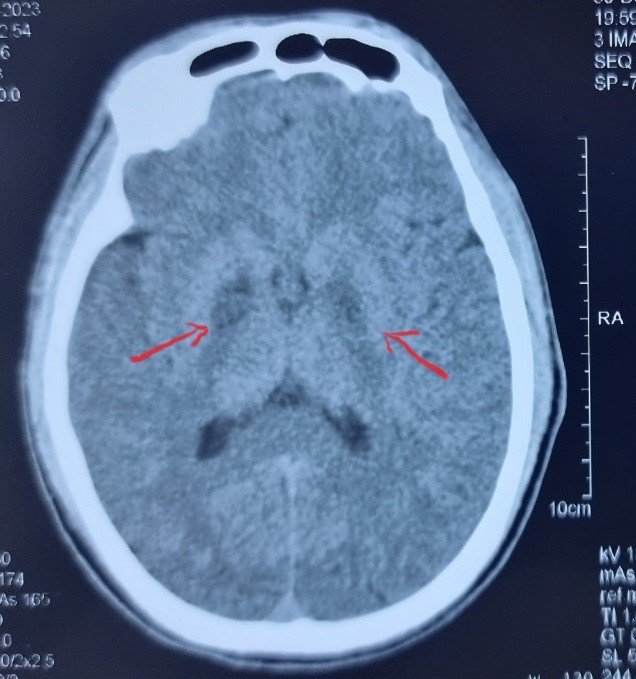

Bệnh nhân nam (31 tuổi tại xã Lóng Luông, huyện Vân Hồ, tỉnh Sơn La) được chuyển đến trong tình trạng hôn mê, suy thận, tổn thương cơ, tổn thương não. Bệnh nhân được chẩn đoán ngộ độc khí CO.

Sau khi điều trị tại Bệnh viện Bạch Mai, bệnh nhân đã có ý thức và tỉnh táo hơn. Bác sĩ Nguyên cho biết đây là một trường hợp rất nặng, có dấu hiệu tổn thương não hai bên rất rõ ràng, có tổn thương cơ, có suy thận…

Bệnh nhân có nguy cơ cao phải đối diện với các biến chứng về tâm thần, thần kinh lâu dài, ví dụ như mất trí nhớ, rối loạn tâm thần, run tay chân, co cứng cơ, liệt,…